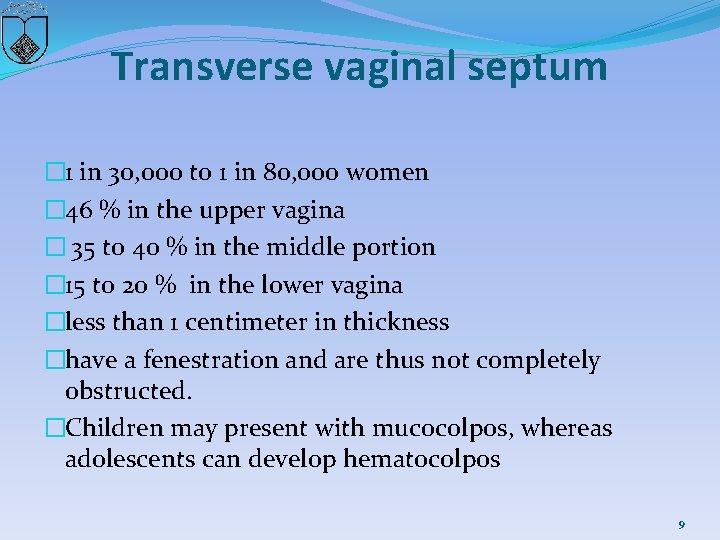

Transverse vaginal septum � 1 in 30, 000 to 1 in 80, 000 women � 46 % in the upper vagina � 35 to 40 % in the middle portion � 15 to 20 % in the lower vagina �less than 1 centimeter in thickness �have a fenestration and are thus not completely obstructed. �Children may present with mucocolpos, whereas adolescents can develop hematocolpos 9